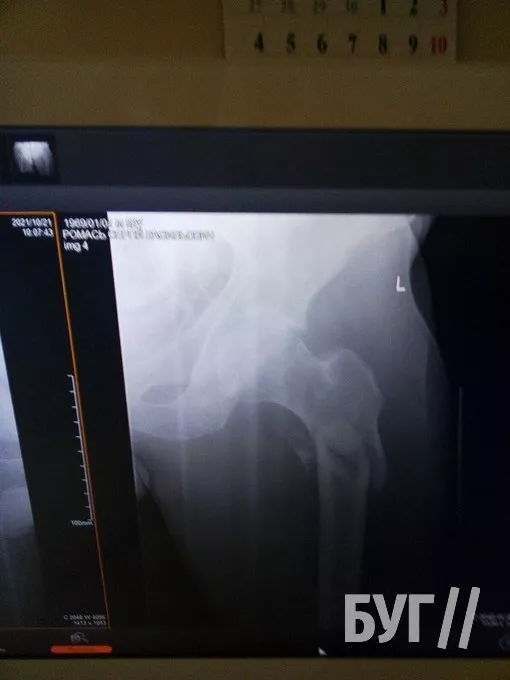

У 52-річного чоловіка, який проживає у селі Суходоли, два переломи стегнових кісток і розтрощений кульшовий суглоб.